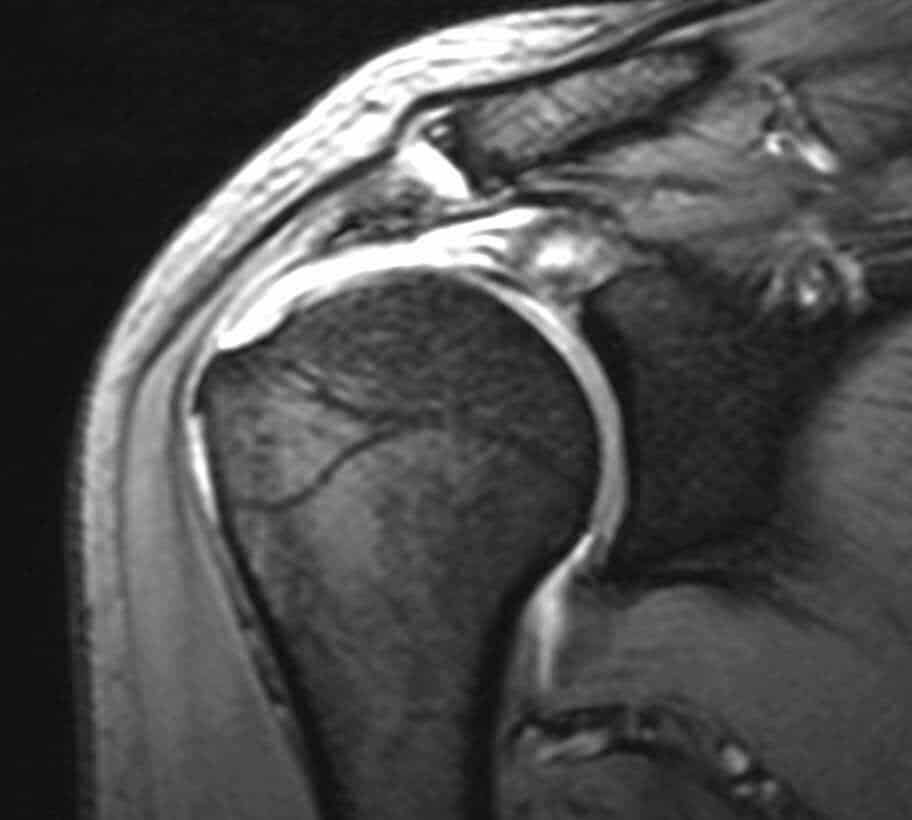

Η έγκαιρη διάγνωση με κλινική εξέταση και απεικονιστικό έλεγχο (υπερηχογράφημα ή μαγνητική τομογραφία) είναι καθοριστική για τη σωστή αντιμετώπιση.

Ο κ. Παναγόπουλος θα λάβει αναλυτικό ιστορικό και θα σας εξετάσει. Μία ακτινογραφία του ώμου θα βοηθήσει να αποκλειστούν άλλα αίτια πόνου, όπως οστεοαρθρίτιδα του ώμου ή ασβεστοποιός τενοντίτιδα. Ο κ. Παναγόπουλος θα σας υποβάλλει σε υπερηχογράφημα ώμου, για να επιβεβαιώσει την παρουσία ρήξεων στο στροφικό πέταλο. Σε ορισμένες περιπτώσεις, ο ιατρός θα σας παραπέμψει για μαγνητική τομογραφία για την αξιολόγηση του μεγέθους της ρήξης ή τυχόν ατροφίας των μυών.

- Η διάγνωση γίνεται με κλινική εξέταση και μαγνητική τομογραφία ή υπερηχογράφημα.